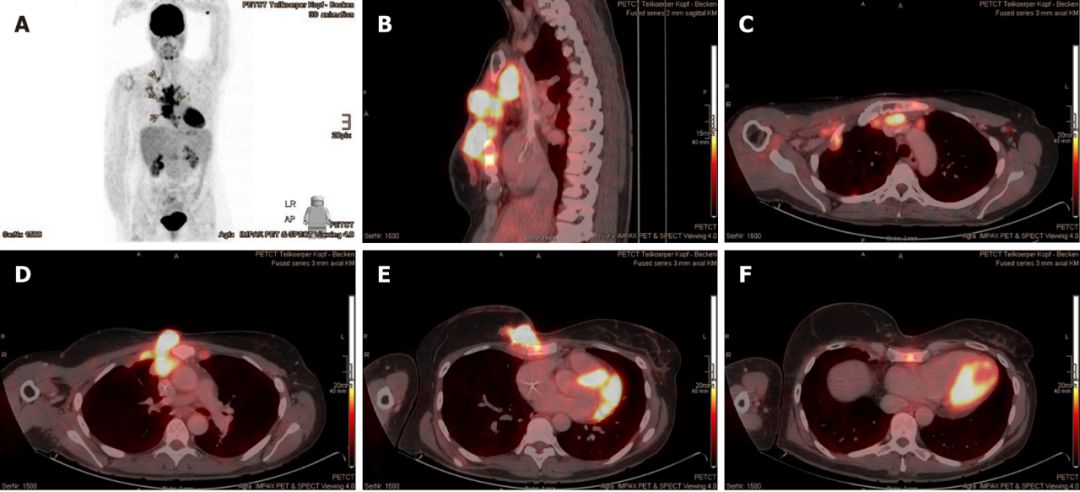

2015年7月,CT扫描发现肿瘤已经侵入肋软骨和腹侧胸膜,她的癌症全面复发了。

这时,Mary已经没有更多的选择,为了降低体内雌激素水平,她切除了双侧卵巢,然后参加了一项氟维司群联合ribociclib的临床试验。2016年2月,由于病情进展,她退出了试验,右侧胸骨的病灶已经达到了30 mm×50 mm×20 mm。

2016年11月至12月,Mary接受了右侧胸骨肿瘤以及邻近胸膜,右侧腋窝,胸骨旁和纵隔区域的淋巴结转移的质子放疗。

01治疗前

幸运的是,Mary对质子治疗的耐受性很好,仅出现了轻微的咳嗽和反流。由于对肺部有一定的辐射剂量,她吃了一些环丙沙星预防放射性肺炎的发生。随后的检查结果显示,癌细胞终于耐不住质子的强烈攻击,开始节节败退,病灶在一次次的缩小。